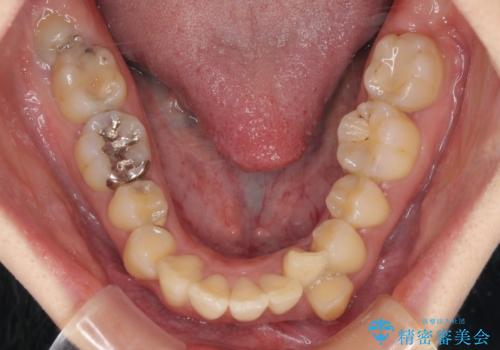

舌の突出癖が顕著で、上顎歯列は完全なV字型となっている状態でした。

下顎歯列にも八重歯があり、上下左右の第一小臼歯4本を抜歯して、ワイヤー装置にて矯正治療を行うこととしました。